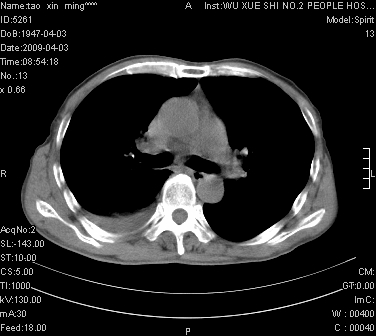

男.62.咯血.胸痛

考虑;肺癌  胸膜转移

考虑肺癌并右侧胸腔积液肺出血

1)考虑右肺下叶周围型肺癌,并右肺下叶肺出血。2)右侧少量胸腔积液。

1)考虑右肺下叶周围型肺癌。2)右侧少量胸腔积液。